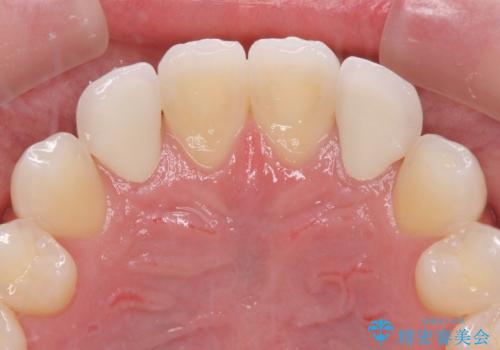

- 前歯のラミネートベニアの不自然な色合いを気にして来院された患者様です。

矯正治療後戻り防止のワイヤー周りにむし歯があったため、オールセラミッククラウンにて補綴することとしました。

ホワイトニングを併用し、治療前と比べて自然でとても明るい口元となりました。